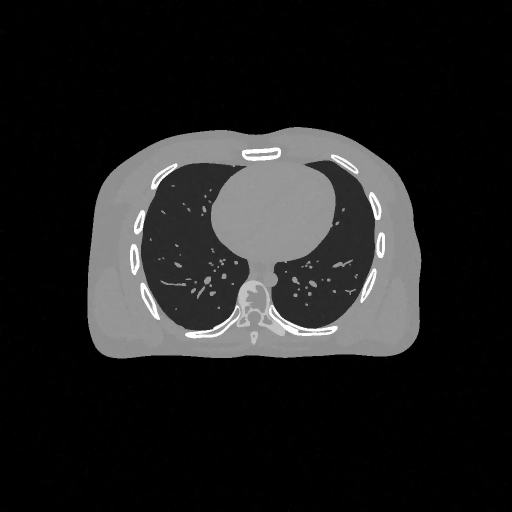

Refer to caption

(a) Ground truth

(b) PDFP, PSNR= 44.94

(c) SPDFP, PSNR= 37.29

(d) SVRG-PDFP, PSNR= 44.98

(e) OPG-ADMM, PSNR= 37.45

(f) SVRG-ADMM, PSNR= 43.82

Figure 5: Reconstructed image (averaged) with different methods over 10 repetitions.

FIG 3 give the results of the peak signal-to-noise ratio (PSNR) of the reconstructed images over time on two devices. It can be seen that stochastic algorithms without SVRG can not get high PSNR comapred to that with SVRG and the full batch PDFP. The performance of SVRG-PDFP is as good as PDPF with the device TITAN RTX while SVRG-PDFP behaves the best with the devices with less cores. FIG 4 record the computational time of different algorithms when PSNRs reach 30,35,37,433035374330,35,37,43 on the two different devices. We can see that when the computational resource is powerful (with many parallel cores), the full-batch PDFP can be highly parallized and the stochastic algorithm does not gain in general. However, when the cores number is not very high, stochastic algorithms with SVRG are beneficial compared to deterministic algorithms. FIG 5 gives the reconstructed images with different algorithms and we can see that the one with SVRG-PDFP achieves the highest PSNR as the full batch PDFP.